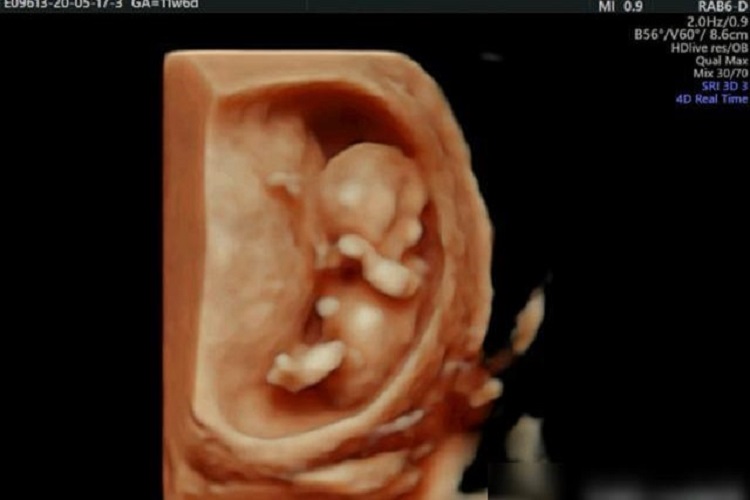

孕十三周时胎儿身长约为9cm,体重约20g,胎儿的四肢可活动,肠管有蠕动,指甲形成。此时通过超声等影像学检查,可基本观测到胎儿形态。孕十三周时胎儿的骨髓、脾等逐渐具有造血功能,可见胸壁运动,肾已存在排尿功能。